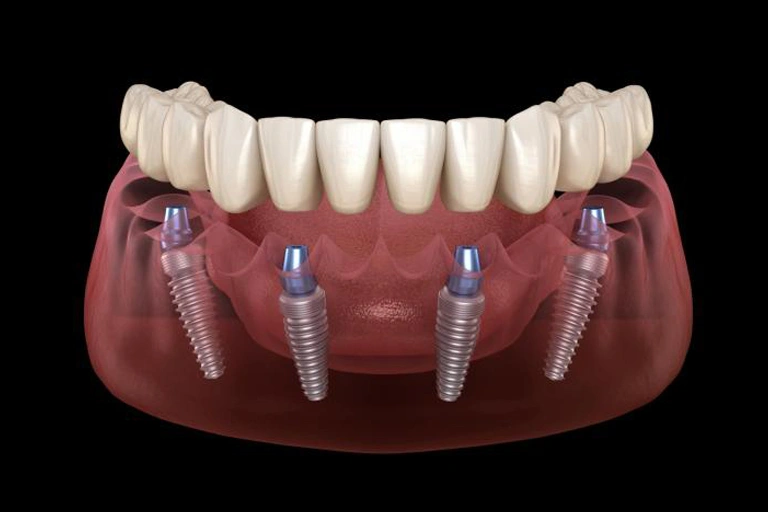

All-on-4 or All-on-6 dental implants are a highly esthetic and comfortable solution for anyone wishing to replace their denture or failing teeth with a fixed arch of teeth. Our Winchester, VA Dental Implant Center only uses the highest top-quality dental implants and components backed by clinical research.

With conventional implants, also called single tooth implants (click here to learn more), you need 12 implants to support the crowns replacing your missing teeth. This means the cost of treatment is very high. Conventional or traditional dental implant treatments also increase the likelihood of requiring a dental bone graft before implants can be placed. With an All-on-4 or All-on-6 dental implant procedure we only require 4 or 6 dental implants to secure a full arch of teeth.

- Complete tooth loss in the upper jaw, lower jaw, or both jaws

- A failing dentition with decay and/or periodontal disease

- A desire for teeth in a day, you receive teeth the same day the procedure is done